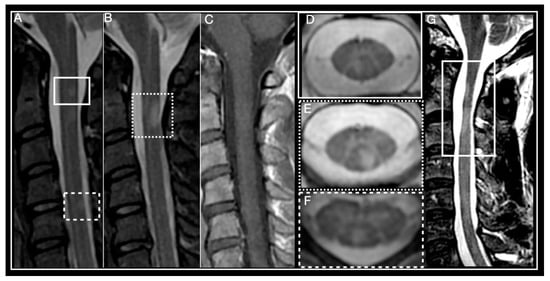

| Spinal cord MRI | Small, peripheral, posterolateral lesions Less than 3 segments Gadolinium enhancement during acute phase | LETM or multiple short segment myelitis Edematous lesions and gadolinium enhancement in acute phase | Central LETM Edematous Necrosis or cavitation Gadolinium enhancement in acute phase | LETM or short myelitis, frequent conus medullaris involvement Linear gadolinium enhancement of the ependymal canal | LETM Central lesions |